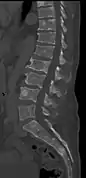

The diagnostic examination of a person with suspected multiple myeloma typically includes a skeletal survey. This is a series of X-rays of the skull, axial skeleton, and proximal long bones. Myeloma activity sometimes appears as "lytic lesions" (with local disappearance of normal bone due to resorption). And on the skull X-ray as "punched-out lesions" (pepper-pot skull). Lesions may also be sclerotic, which is seen as radiodense.[47] Overall, the radiodensity of myeloma is between −30 and 120 Hounsfield units (HU).[48] Magnetic resonance imaging is more sensitive than simple X-rays in the detection of lytic lesions, and may supersede a skeletal survey, especially when vertebral disease is suspected. Occasionally, a CT scan is performed to measure the size of soft-tissue plasmacytomas. Bone scans are typically not of any additional value in the workup of people with myeloma (no new bone formation; lytic lesions not well visualized on bone scan).

CT scan of the lower vertebral column in a man with multiple myeloma, showing multiple osteoblastic lesions: These are more radiodense (brighter in this image) than the surrounding cancellous bone, in contrast to osteolytic lesions, which are less radiodense.